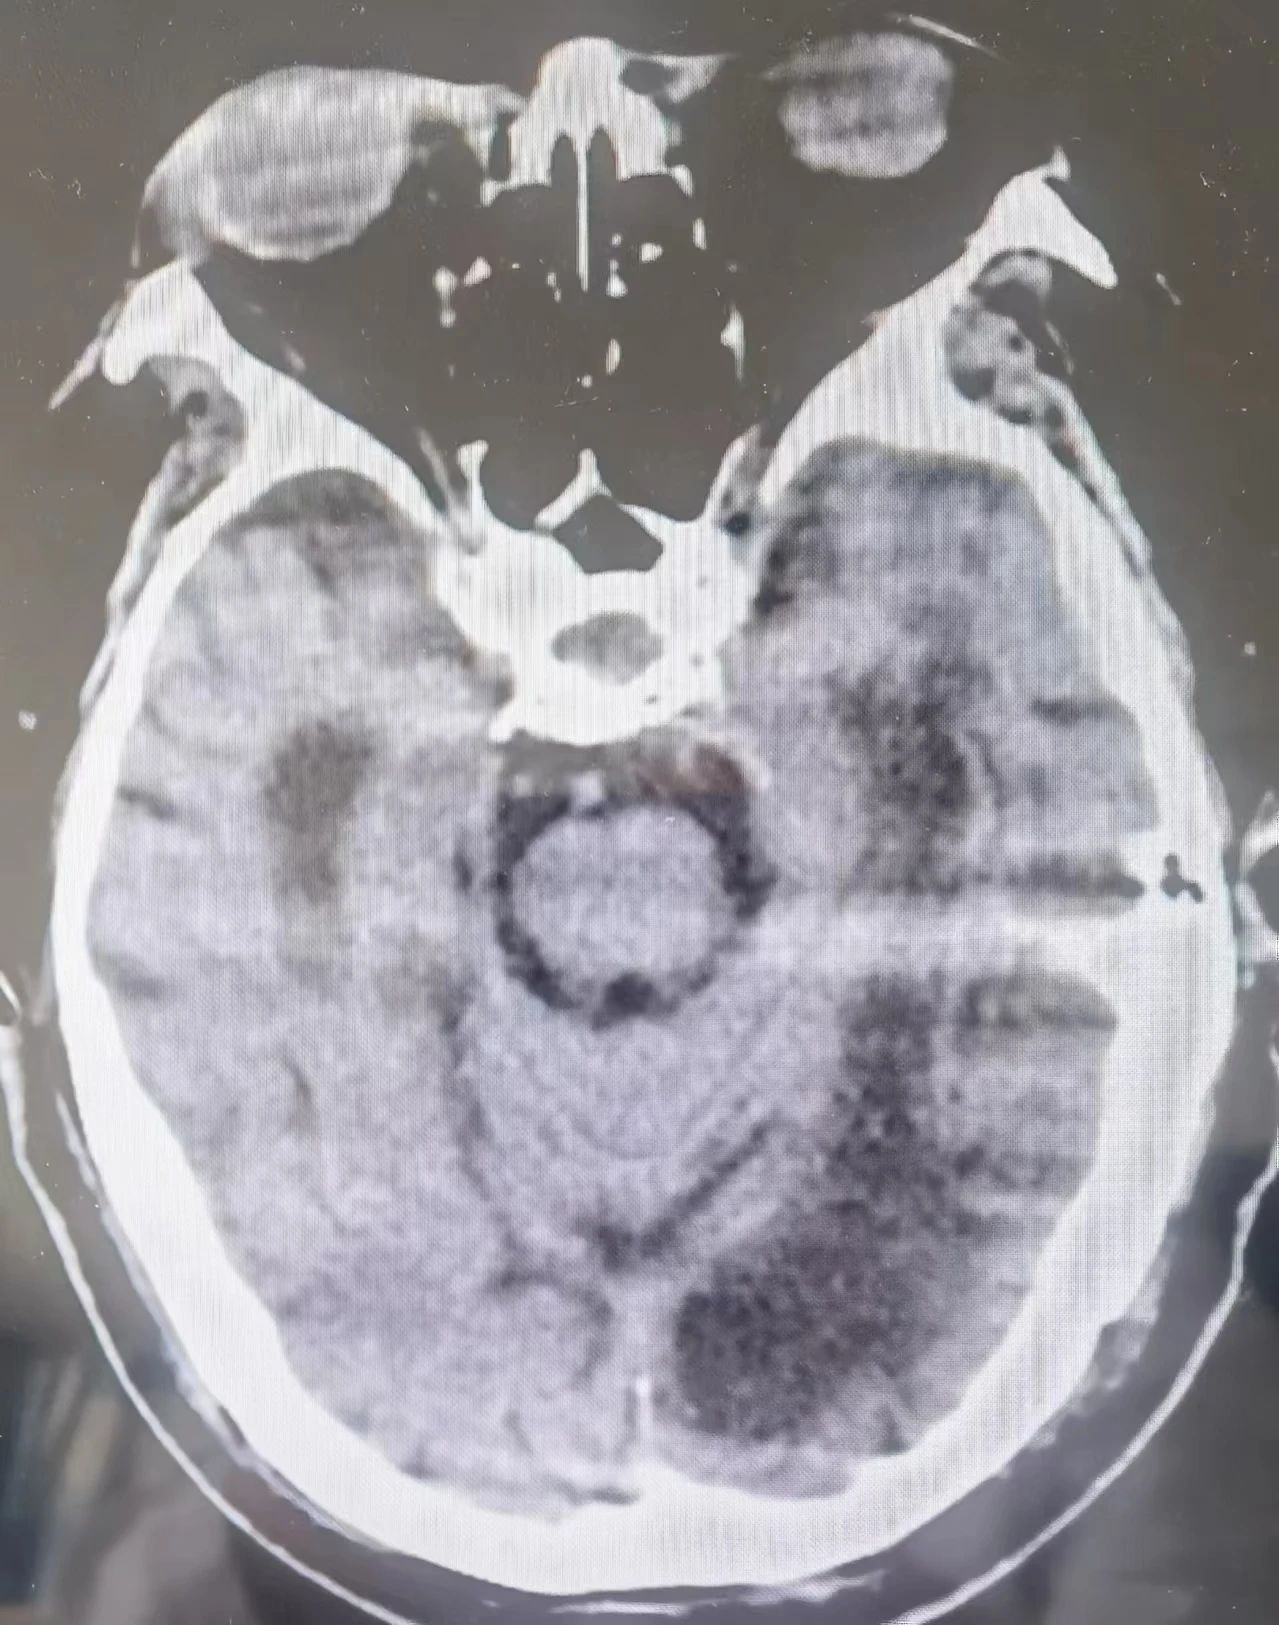

(患者入院时头部CT)

老年病科主任王珺接诊后,立即给予患者抗痫药物,第一时间稳定病情,但好景不长,由于患者癫痫状态过长(超过24小时),并且合并有30年高血压、糖尿病,15年脑梗,3年重度脑痴呆病史,自身抵抗力相对较弱,单一广普抗癫痫药物作用有限,于是王主任当即决定将三种抗癫药联合应用,迅速降颅压、减轻脑水肿、纠正乏氧、醒脑开窍、营养脑细胞,当即便缓解了症状,癫痫状态由持续性发作减轻为间断性作、部分发作。在老年病科医护人员多日的治疗和精心照护下,住院第六天,患者癫痫症状消失,住院第八天,顺利痊愈出院。